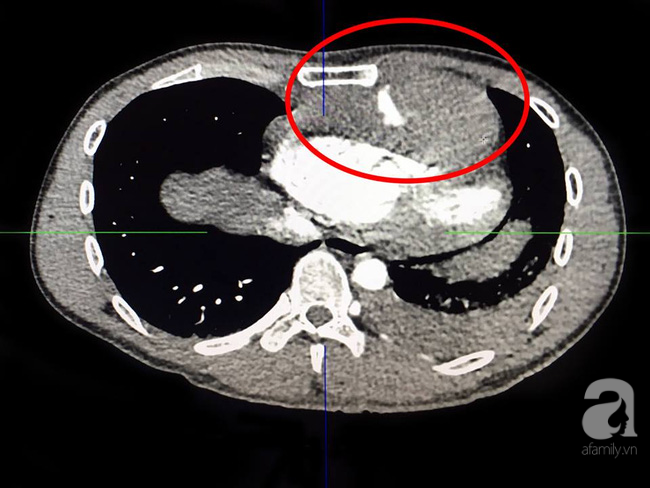

Ảnh chụp phim cho thấy có khối máu lớn làm chèn ép tim.

Các BS nhanh chóng chỉ định các cận lâm sàng cần thiết. Kết quả chụp phim cho thấy bệnh nhân bị đứt động mạch ngực trong bên trái, có khối máu tụ lớn ở trung thất trước chèn ép tim, tràn máu màng phổi, phải lập thuật ngay để mong bảo toàn tính mạng.